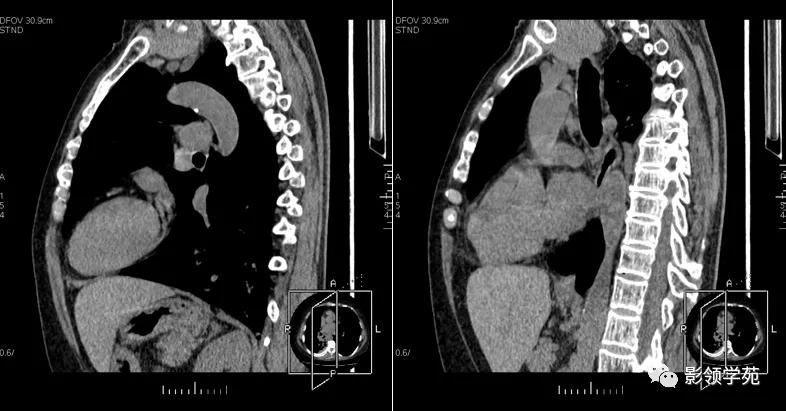

1、多数病灶与颈部甲状腺相延续,多位于气管前间隙,亦可伸入到气管及食道后方,冠状位及矢状位重建有利于显示连续关系。

2、肿块边缘较光滑,密度多不均匀,可见单发或多发低密度区,钙化较常见。

3、平扫CT值较高,增强后强化明显,且延迟较长时间。

4、多数病例纵隔内大血管及气管有推移表现。

矢状位重建显示更清晰